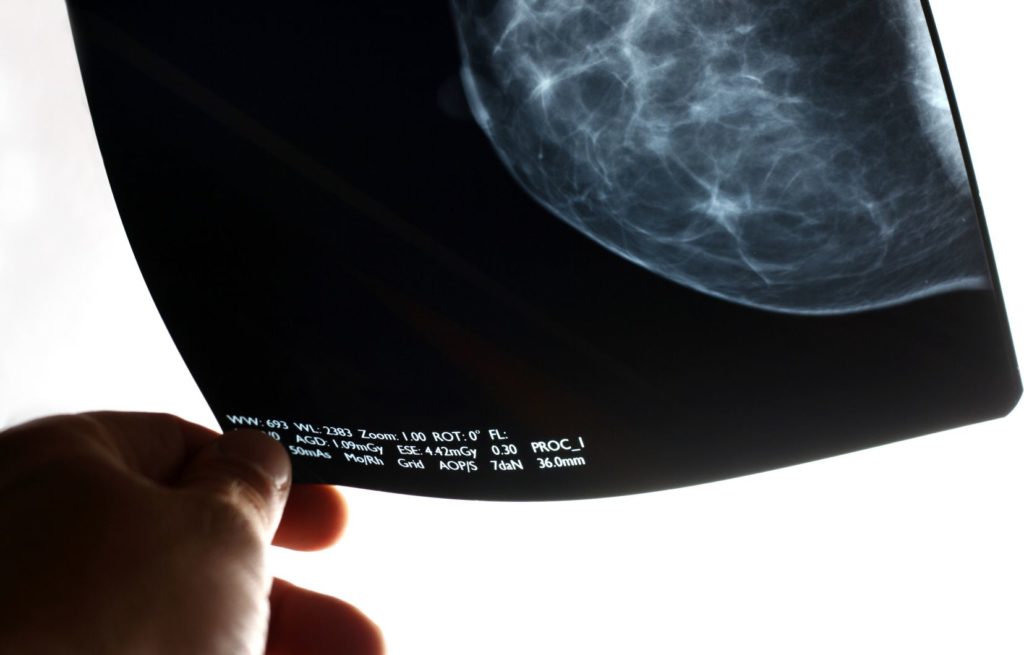

(Jean-Benoit Legault/ Le Devoir) — Les diagnostics de cancer ont connu un déclin important depuis le début de la pandémie, confirme un nouveau sondage dont les résultats ont été dévoilés en primeur à La Presse canadienne à l’occasion de la Journée mondiale contre le cancer.

Les 141 participants à l’enquête rapportent un déclin de 12 % des diagnostics de cancer colorectal, de 16 % pour le cancer du poumon, de 18 % pour le cancer de la prostate et de 19 % pour le cancer du sein.